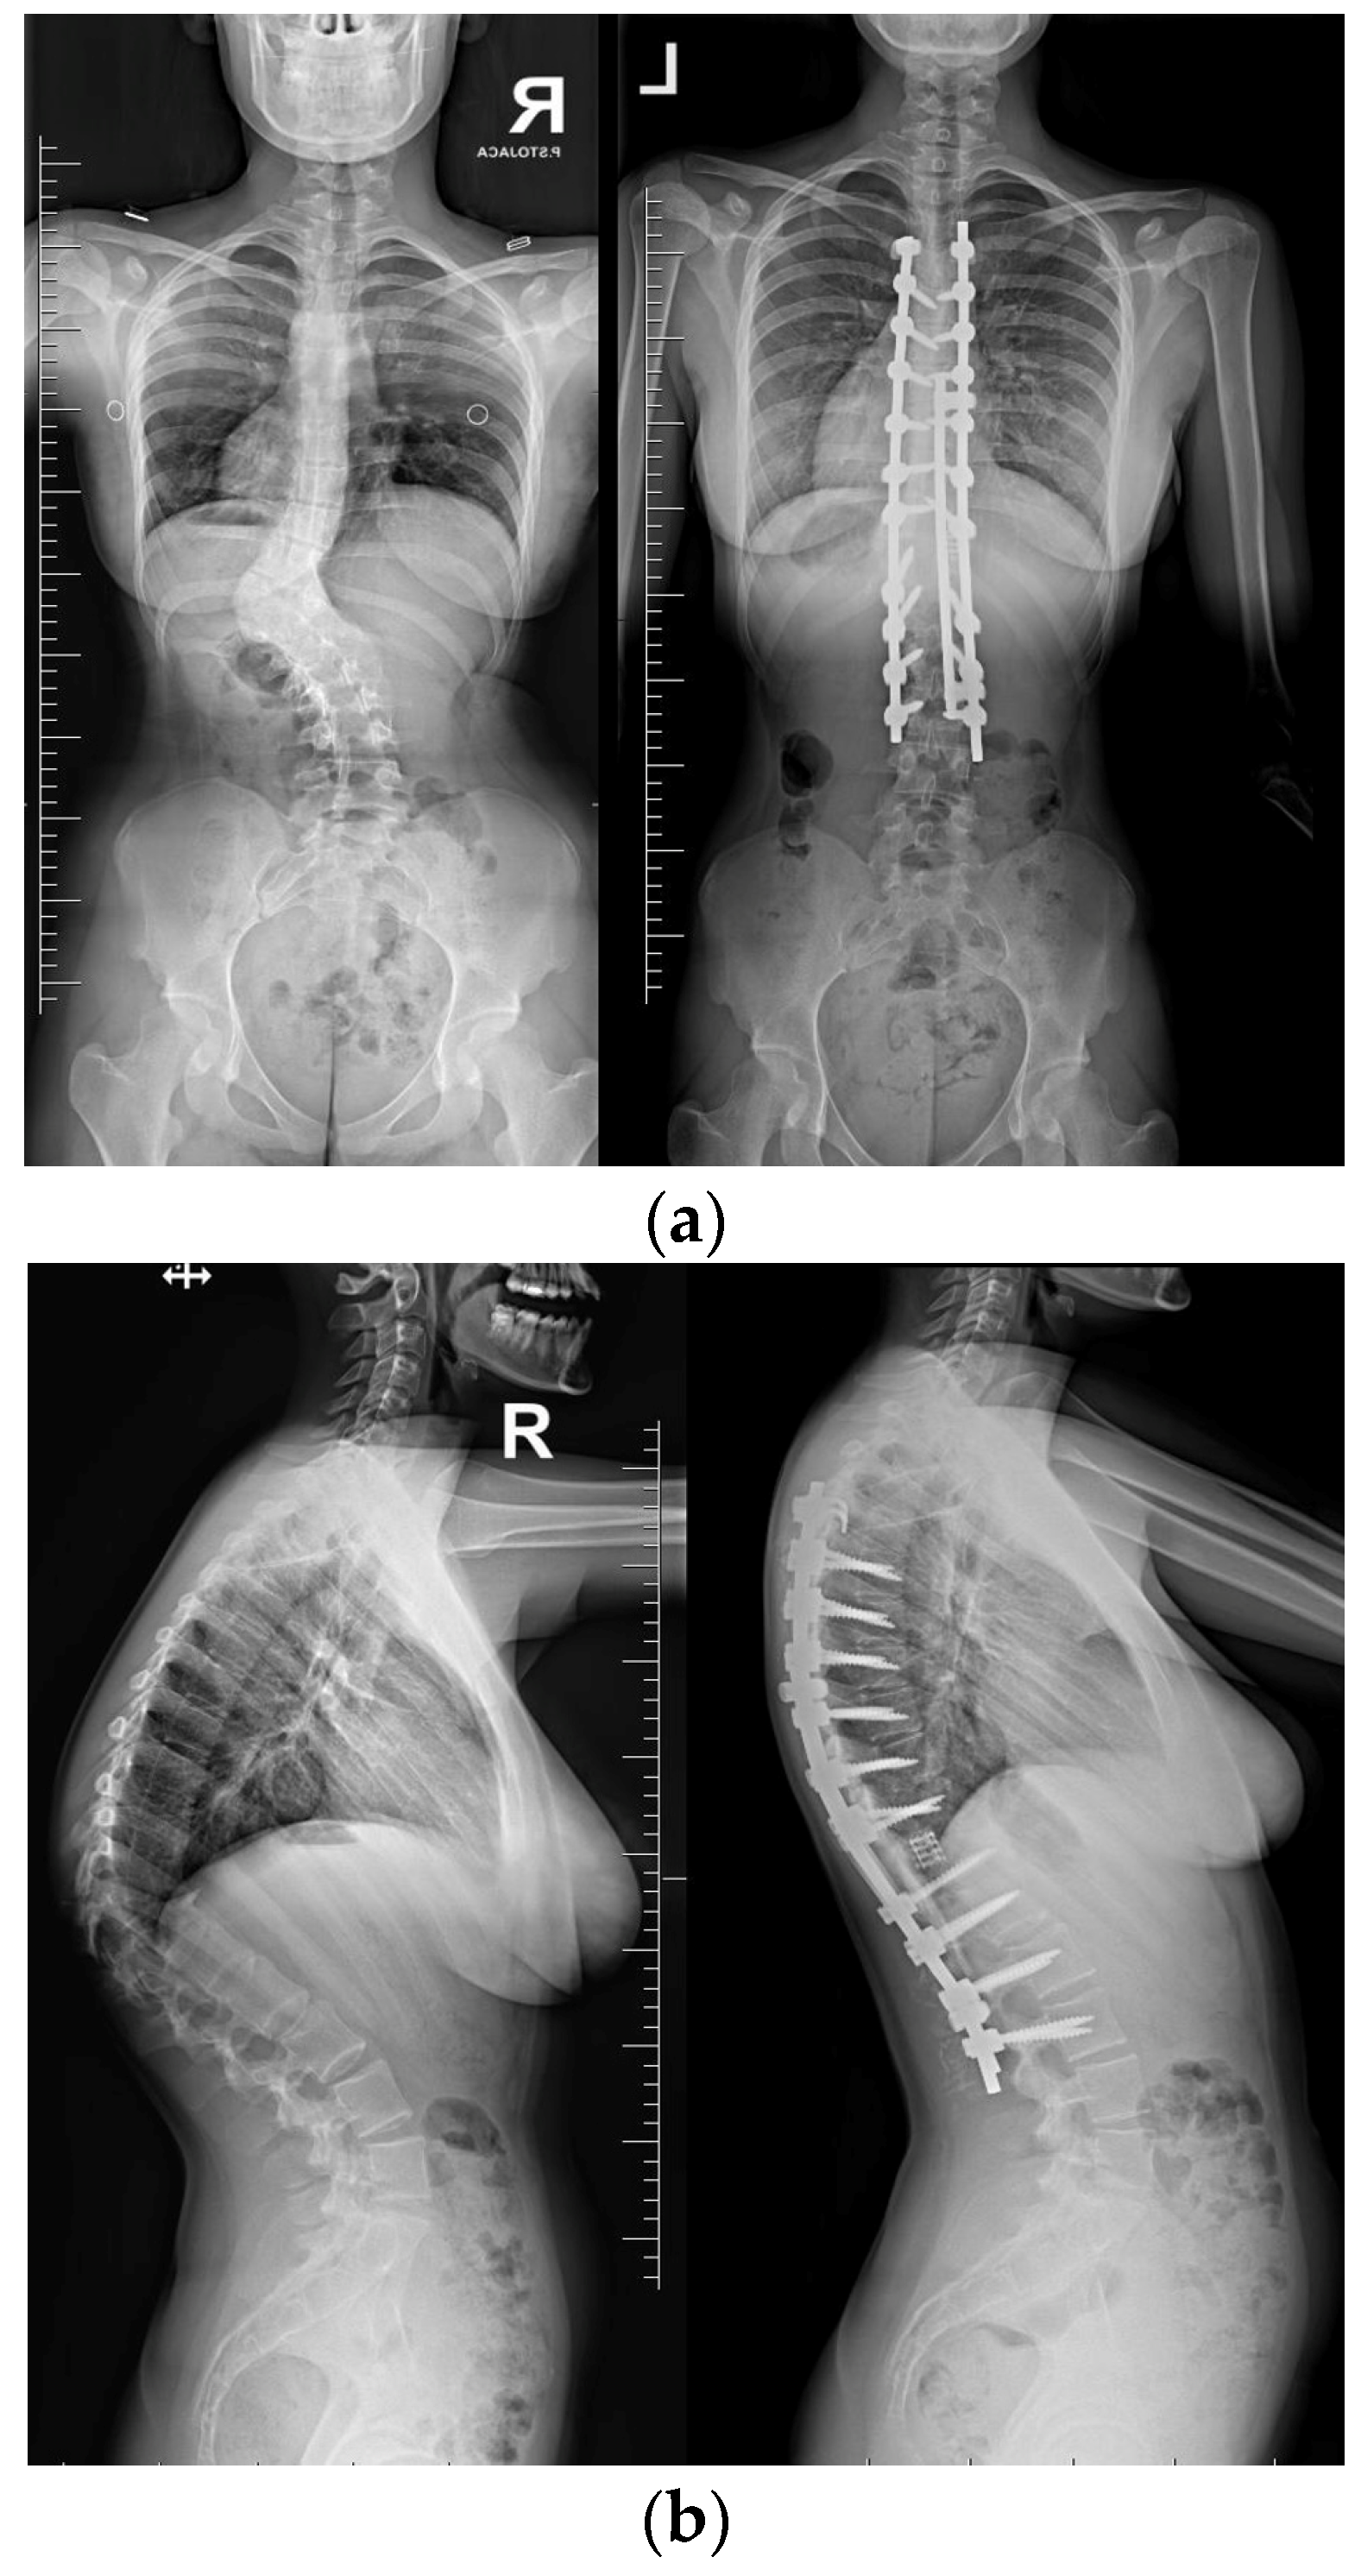

Neurological examinations showed full strength (5/5) in all major muscle groups of BUE/BLE, sensation intact throughout, normal reflexes (including abdominal), and pain on palpation in the thoracic spine above and below the gibbous. The neuro-imaging findings indicated a Cobb angle of 63° in the main thoracolumbar curve. The flexibility of the curve was measured at 63° when bending, decreasing to 48°. Additionally, there was a thoracic kyphosis of 4° between T2 and T5 and 32° between T5 and T12, with a severe focal thoracic kyphosis of 108° (Figure 2).

Figure 2. Standard standing AP and lateral X-rays and side-bending films of the 16-year-old female before surgical treatment. These X-rays showed severe and stiff congenital kyphosis.